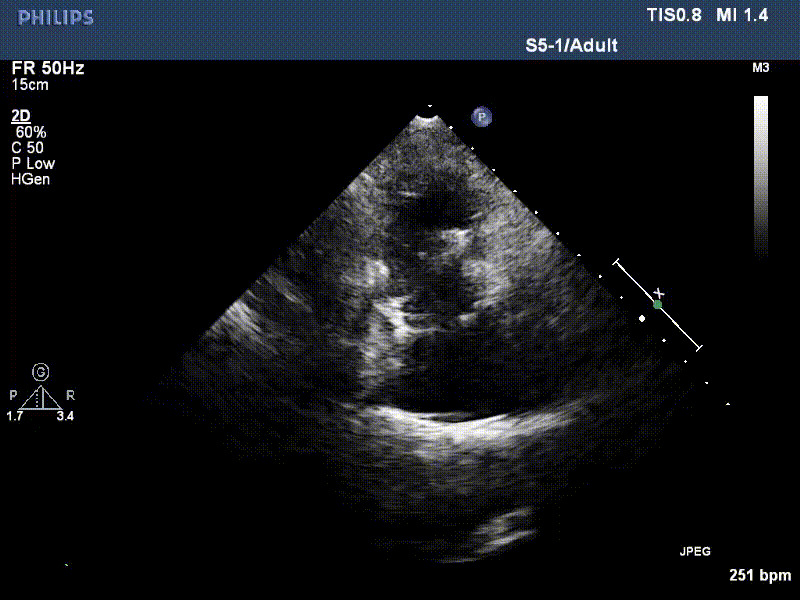

流并分別伴有房顫和房撲,高外科手術(shù)風險。術(shù)前超聲提示,兩例患者下腔靜脈寬度分別為13mm和29mm,右房內(nèi)徑(上下徑和左右徑)分別為52×41mm和53×43mm,彩色多普勒顯示極重度三尖瓣反流,VCW分別為14×15mm和10mm。

1年前,兩例患者因難治性雙下肢水腫輾轉(zhuǎn)多家醫(yī)院尋求救治,考慮到兩例患者高齡、基礎(chǔ)疾病多、STS評分高,不適合傳統(tǒng)外科開胸手術(shù),葛均波院士及其團隊周達新教授、潘文志教授、張源博士、陳莎莎博士、陳丹丹博士聯(lián)合心外科王春生、魏來主任,麻醉科繆長虹、郭克芳主任以及心超室的潘翠珍教授、李偉教授共同討論決定,采用我國創(chuàng)新器械LuX-Valve Plus經(jīng)血管三尖瓣置換系統(tǒng)為患者進行手術(shù)。相較于第一代產(chǎn)品LuX-Valve,LuX-Valve Plus經(jīng)血管三尖瓣置換系統(tǒng)對輸送系統(tǒng)進行了全面升級,實現(xiàn)了經(jīng)頸靜脈入路的方式,進一步減小了手術(shù)風險和對患者的創(chuàng)傷。目前隨訪1年心超結(jié)果顯示,三尖瓣極重度反流消失,人工三尖瓣瓣膜穩(wěn)定牢固,瓣葉活動度良好,右心室及下腔靜脈明顯縮小,心輸出量增加。兩位老人手術(shù)后沒有出現(xiàn)過胸悶氣促的癥狀,下肢水腫緩解,活動耐力提升,生活質(zhì)量也大為提高。

圖2 患者植入LuX-Valve Plus后,1年隨訪心超提示無三尖瓣反流